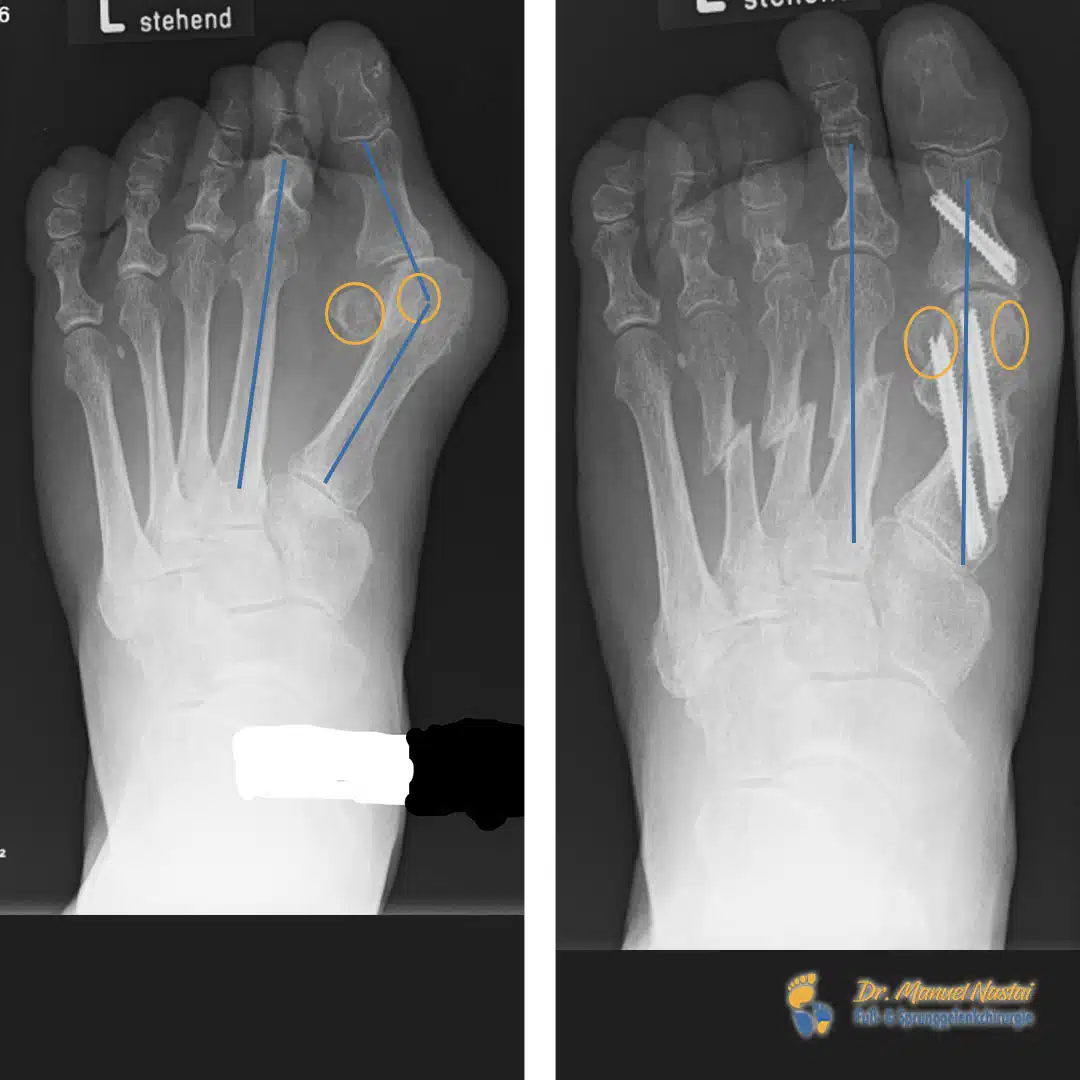

Links (präoperativ): Deutlicher Hallux valgus mit vergrößertem Intermetatarsalwinkel IMA 1–2 (blaue Linien markieren die Längsachsen von M1 und M2; die Spreizung ist klar erweitert). Die Sesambeine unter dem Großzehengrundgelenk (orange markiert) sind nach lateral verlagert und liegen nicht mehr zentral unter dem Metatarsalköpfchen – Ausdruck der Subluxation im MTP-I. Zusätzlich zeigt sich ein Hochstand / Beugerfixation der 2. Zehe: der 2. Strahl steht in Fehlstellung, was zur Überlastung/Transfermetatarsalgie neigt.

Rechts (postoperativ): Korrektur der Großzehenachse mit deutlich reduziertem IMA; die blauen Achsen von M1 und M2 verlaufen nun annähernd parallel (= Parallelisierung der Strahlen). Die Sesambeine (orange) sind rezentriert und wieder regelrecht unter dem ersten Metatarsalköpfchen positioniert. Die implantierten Schrauben sichern die Korrektur am 1. Strahl stabil. Die 2. Zehe zeigt eine aufgerichtete, belastungsfähige Stellung ohne Hochstand/Beugekontraktur.